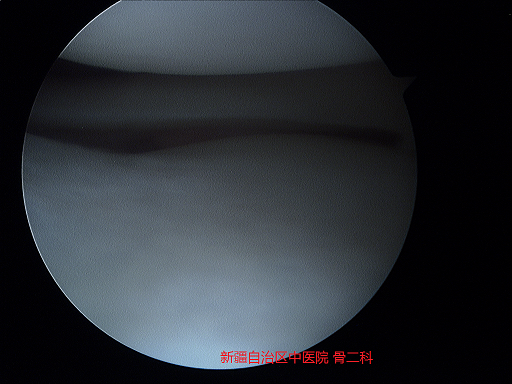

4.半月板损伤的危害

半月板损伤如果没有得到及时的处理,会在反复的卡压过程中造成不可逆的软骨损伤,这种情况即使处理了半月板,膝关节功能也不能恢复如前。

关节镜微创术后残留软骨损伤